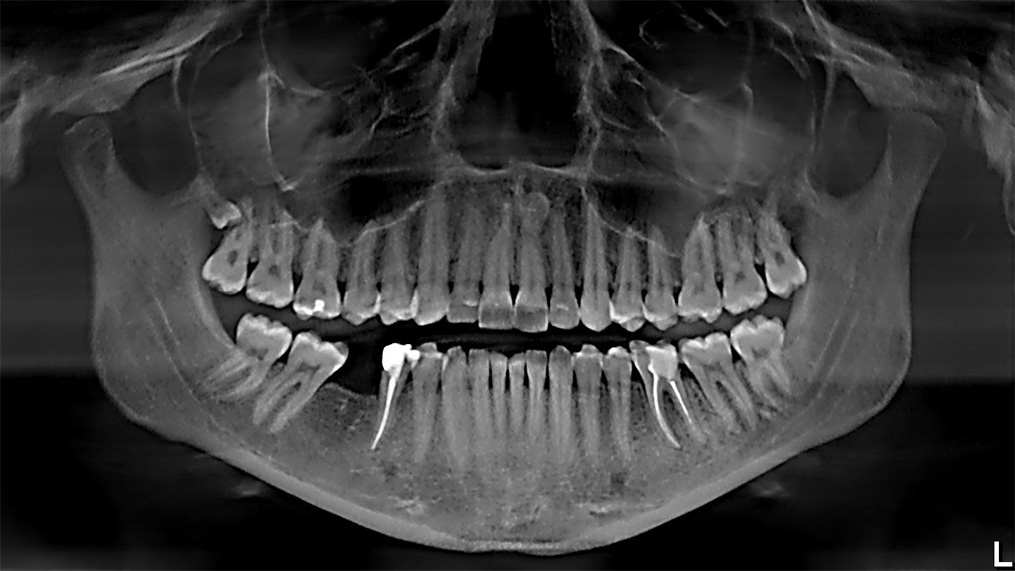

снимок не мой, КДПВ, понятное дело...

Сделали снимок, вроде что-то видно. Врач лазил пальцами с полчаса, пытаясь поддеть, но это было невозможно. Выдали рекомендации залить в лунку какого-то лекарства и наблюдать за состоянием. При повышении температуры (инфекция, нагноение) - бежать в очередь на операцию, на разрез.